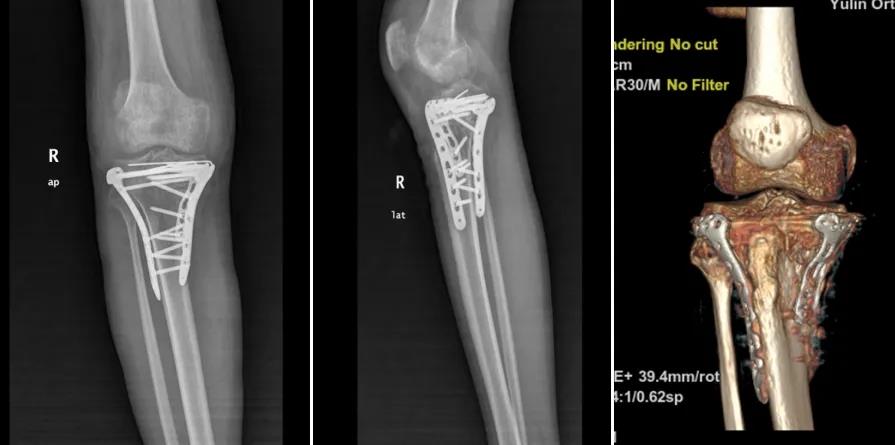

手术当日,作为主刀的朱博副主任医师,凭借精细入微的操作和手术团队的高效协作,这台被视为“极高难度”的手术一气呵成,仅历时两小时便顺利完成。术后,朱博副主任及主管卜庭用医师对罗某的康复极为重视,亲自指导其进行系统性的膝关节功能康复训练。

在科室医护人员的精心治疗与照护下,罗某恢复迅速:复查片显示骨折对位对线良好,关节面平整,膝关节疼痛显著缓解,关节活动度大幅改善。久违的笑容终于回到他的脸上:“是玉林市中西医结合骨科医院的专家们,给了我重新站起来的机会!手术技术太强了,感谢朱主任、卜医生和所有医护人员!”